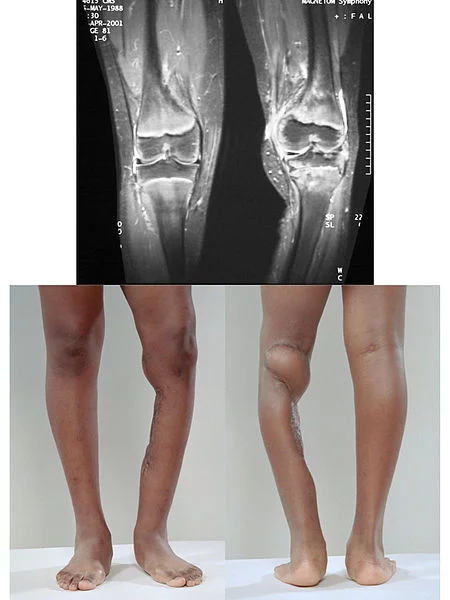

短肢畸形

短肢来自畸形(micromelia)是指脊椎动物中所出现的四肢特短的畸型。

尤其是长骨发生异常,除遗传之外,也可由人工对鸡胚作胰岛素注射和维生素B2、生物素来自不足等所引起。人也可由于thalidomide而出现同样的畸形,严重时可以形成好像四肢末端直接生在躯干上似的那样形状,称海豹肢畸形(phocomelia)。偶尔也可见到四肢缺少的无肢(ame360百科lia)类型,这是特殊情况。